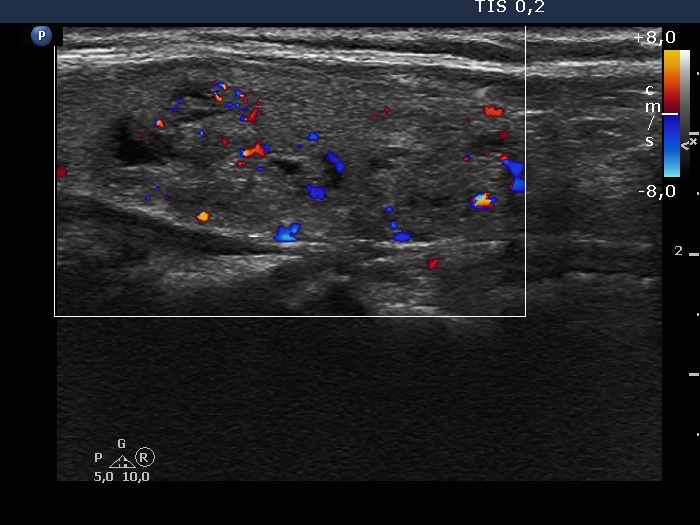

Left lobe, longitudinal scan, color Doppler mode. The vascularity is not specific.